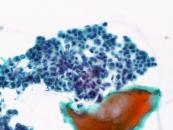

第38回日本臨床細胞学会九州連合会学会(熊本)スライドカンファレンス症例4

種別:泌尿器

出題:石原 明 潤和会記念病院病理診断科

| 年齢 | 70代 | 性別 | 男性 |

| 採取部位 | 尿 | 採取方法 | 自然尿 |

| 検体処理法 | LBC法(サイトリッチレッド、BD SurePath) |

既往歴:高血圧、心房細動、左鼠径ヘルニア手術。

現病歴:10ヶ月前 肉眼的血尿(主訴)、4ヶ月前 近医受診し、PSA値24.5、膀胱鏡にて前立腺部尿道の乳頭状

腫瘍指摘、当院紹介受診。

画像診断では左外鼠径・内外腸骨・総腸骨各リンパ節腫大。

臨床診断:前立腺癌・転移あり、尿道部尿路上皮癌。

| 正解 | 4. 前立腺導管型腺癌 |

▼選択肢及び投票結果

| 1.扁平上皮癌 | 0件 | (0.0%) | |

| 2. 尿路上皮癌 HGUC | 17件 | (16.3%) | |

| 3. 神経内分泌癌 | 0件 | (0.0%) | |

| 4. 前立腺導管型腺癌 | 84件 | (80.8%) | |

| 5. 前立腺尿道ポリープ | 3件 | (2.9%) | |

| 投票総数 | 104件 | (100%) |